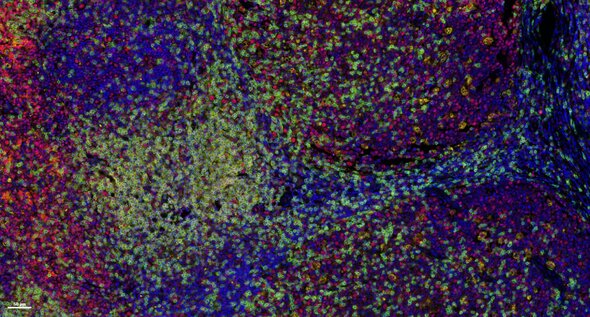

Multiplex immunofluorescence (mIF) is a powerful technique that allows researchers to simultaneously visualize and analyze multiple components of the tissue microenvironment. Multiplexing uses multiple antibodies with fluorescent detection to target specific proteins within the microenvironment, allowing researchers to create a detailed map of the various cells, proteins and their interactions. We offer both low plex and high plex options for mIF which allow you to profile tissues to determine cell phenotypes, their functional state, and cell interactions.

Two side-by-side grids of purple circular spots, one on a white background and one on a dark background, showing texture variation